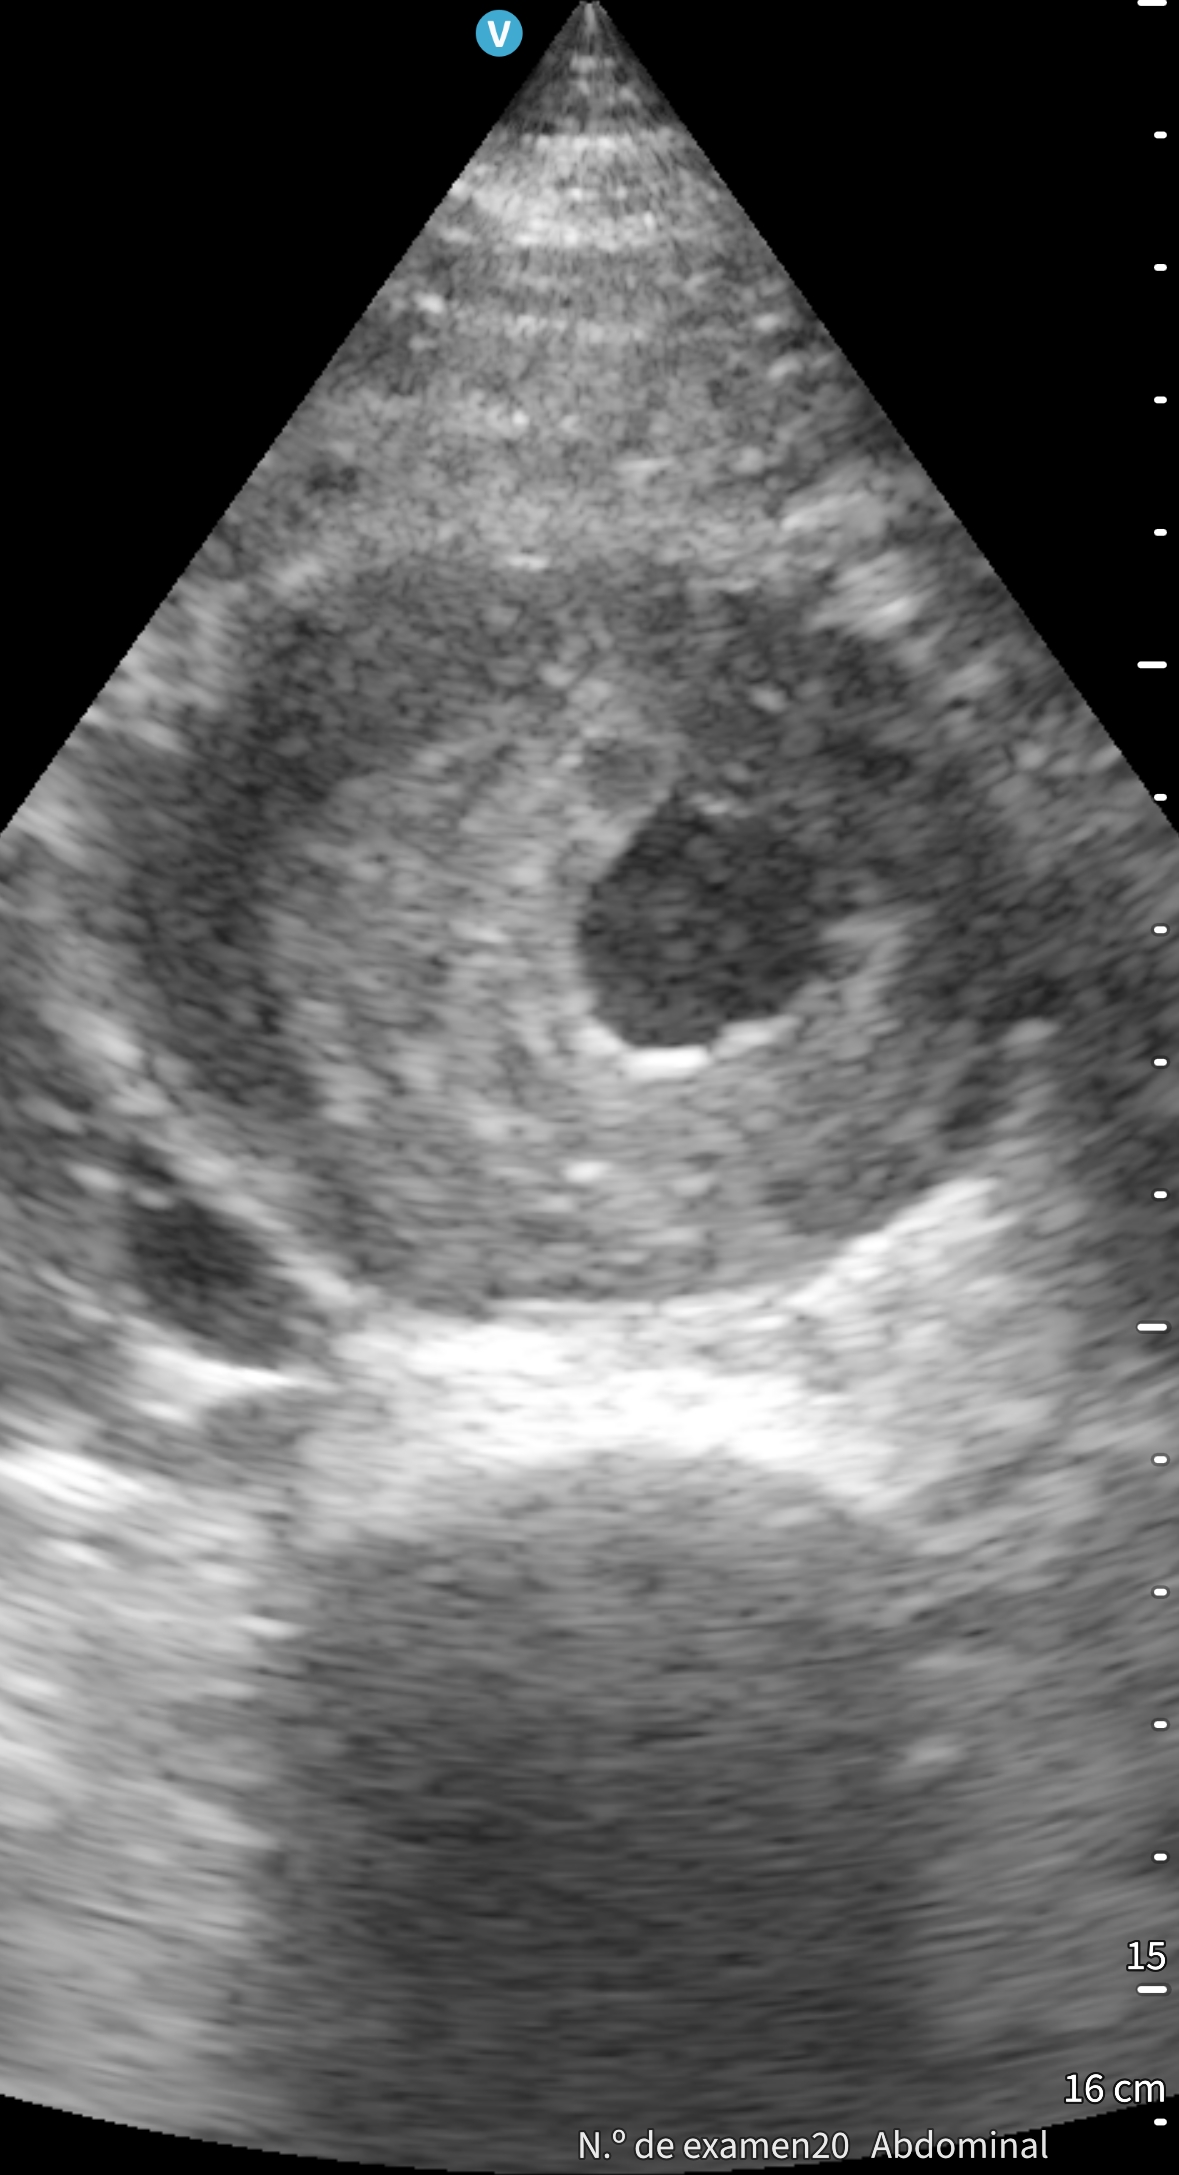

Tras finalizar una sesión de diálisis desarrolla hipotensión sintomática y dolor lumbar. A su llegada a urgencias presenta TA 60/40 mmHg, palidez mucocutánea y exploración abdominal anodina. Se inicia fluidoterapia. Ante la sospecha de rotura aneurismática se realiza ecografía a pie de cama, que muestra aneurisma de aorta abdominal con trombo mural irregular y luz permeable reducida, sin signos de rotura, permitiendo descartar una emergencia tiempo-dependiente. El angioTAC urgente confirma la ausencia de disección o extravasación, aunque evidencia crecimiento aneurismático respecto a estudios previos. Analítica sin anemia aguda, ligera leucocitosis y troponinas discretamente elevadas sin ascenso dinámico. Evoluciona favorablemente con recuperación tensional y resolución del dolor.

La ecografía clínica a pie de cama resultó fundamental para descartar de forma rápida una rotura aneurismática y dirigir el manejo inicial. Este caso demuestra su valor como herramienta resolutiva, segura y accesible en urgencias, reforzando la capacidad diagnóstica y la toma de decisiones del profesional de Medicina de Familia.